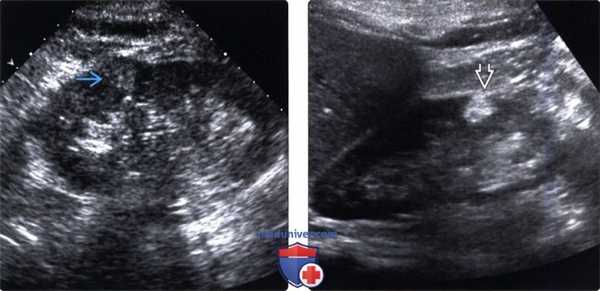

(Левый) На продольном УЗ срезе визуализируется мелкий, гиперэхогенный, светлоклеточный ПКР с частично экзофитным ростом, который можно ошибочно принять за ангиомиолипому. Дифференцировать можно по наличию большого количества жировой ткани при КТ или МРТ.

(Правый) На продольном ультразвуковом срезе у пациента с ангиомиолипомой визуализируется мелкое гиперэхогенное образование в корковом веществе. Эхогенность выше, чем в вышеописанном ПКР. Цветовой ток отсутствует. Подтвердить диагноз можно при КТ или МРТ.